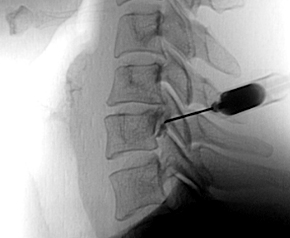

대퇴골두의 혈액순환 장애로 뼈 조직이 괴사되고 괴사된 뼈에 압력이 지속적으로 가해져 괴사부 위가 골절되면서 통증이 나타나는 질환입니다.

신경차단술

주요 원인과 증상

원인

· 과도한 음주습관

· 스테로이드제(호르몬제) 남용

· 외상으로 인한 고관절의 탈구와 골절

· 당뇨 후유증 및 혈액순환 장애

증상

· 사타구니가 뻐근하고 보행시 엉덩이 부위가 쑤심과 통증

· 엉덩이, 허벅지, 골반 등 통증 발생

· 양반다리와 같이 다리를 벌린 자세가 어려움

· 장시간 보행시 고관절 전체의 통증 발생

치료

보존적 치료

통증을 줄이는 비스테로이드 소염진통제 등의 약물치료, 주사치료 및 운동치료, 도수치료, 체외충격파 치료등을 시행합니다.

수술적 치료

괴사가 많이 진행된 경우 손상된 관절을 인공관절로 대체하여 통증을 없애고 일상생활을 가능하게 합니다.